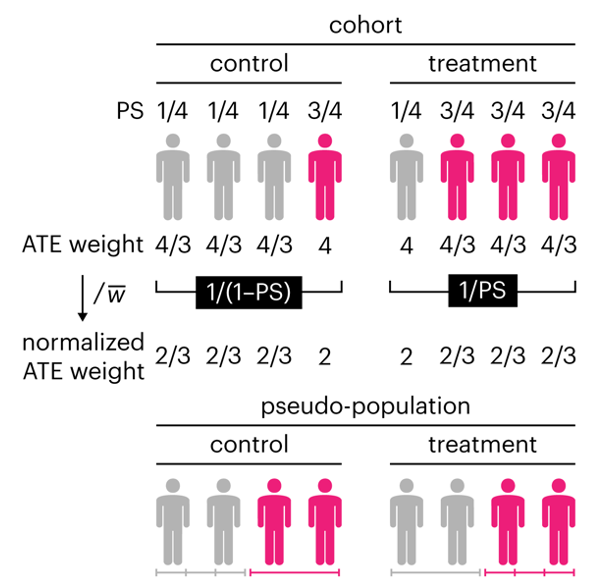

Propensity score weighting

This month, we explore a related and powerful technique to address bias: propensity score weighting (PSW), which applies weights to each subject instead of matching (or discarding) them.

Kurz, C.F., Krzywinski, M. & Altman, N. (2025) Points of significance: Propensity score weighting. Nat. Methods 22:1–3.